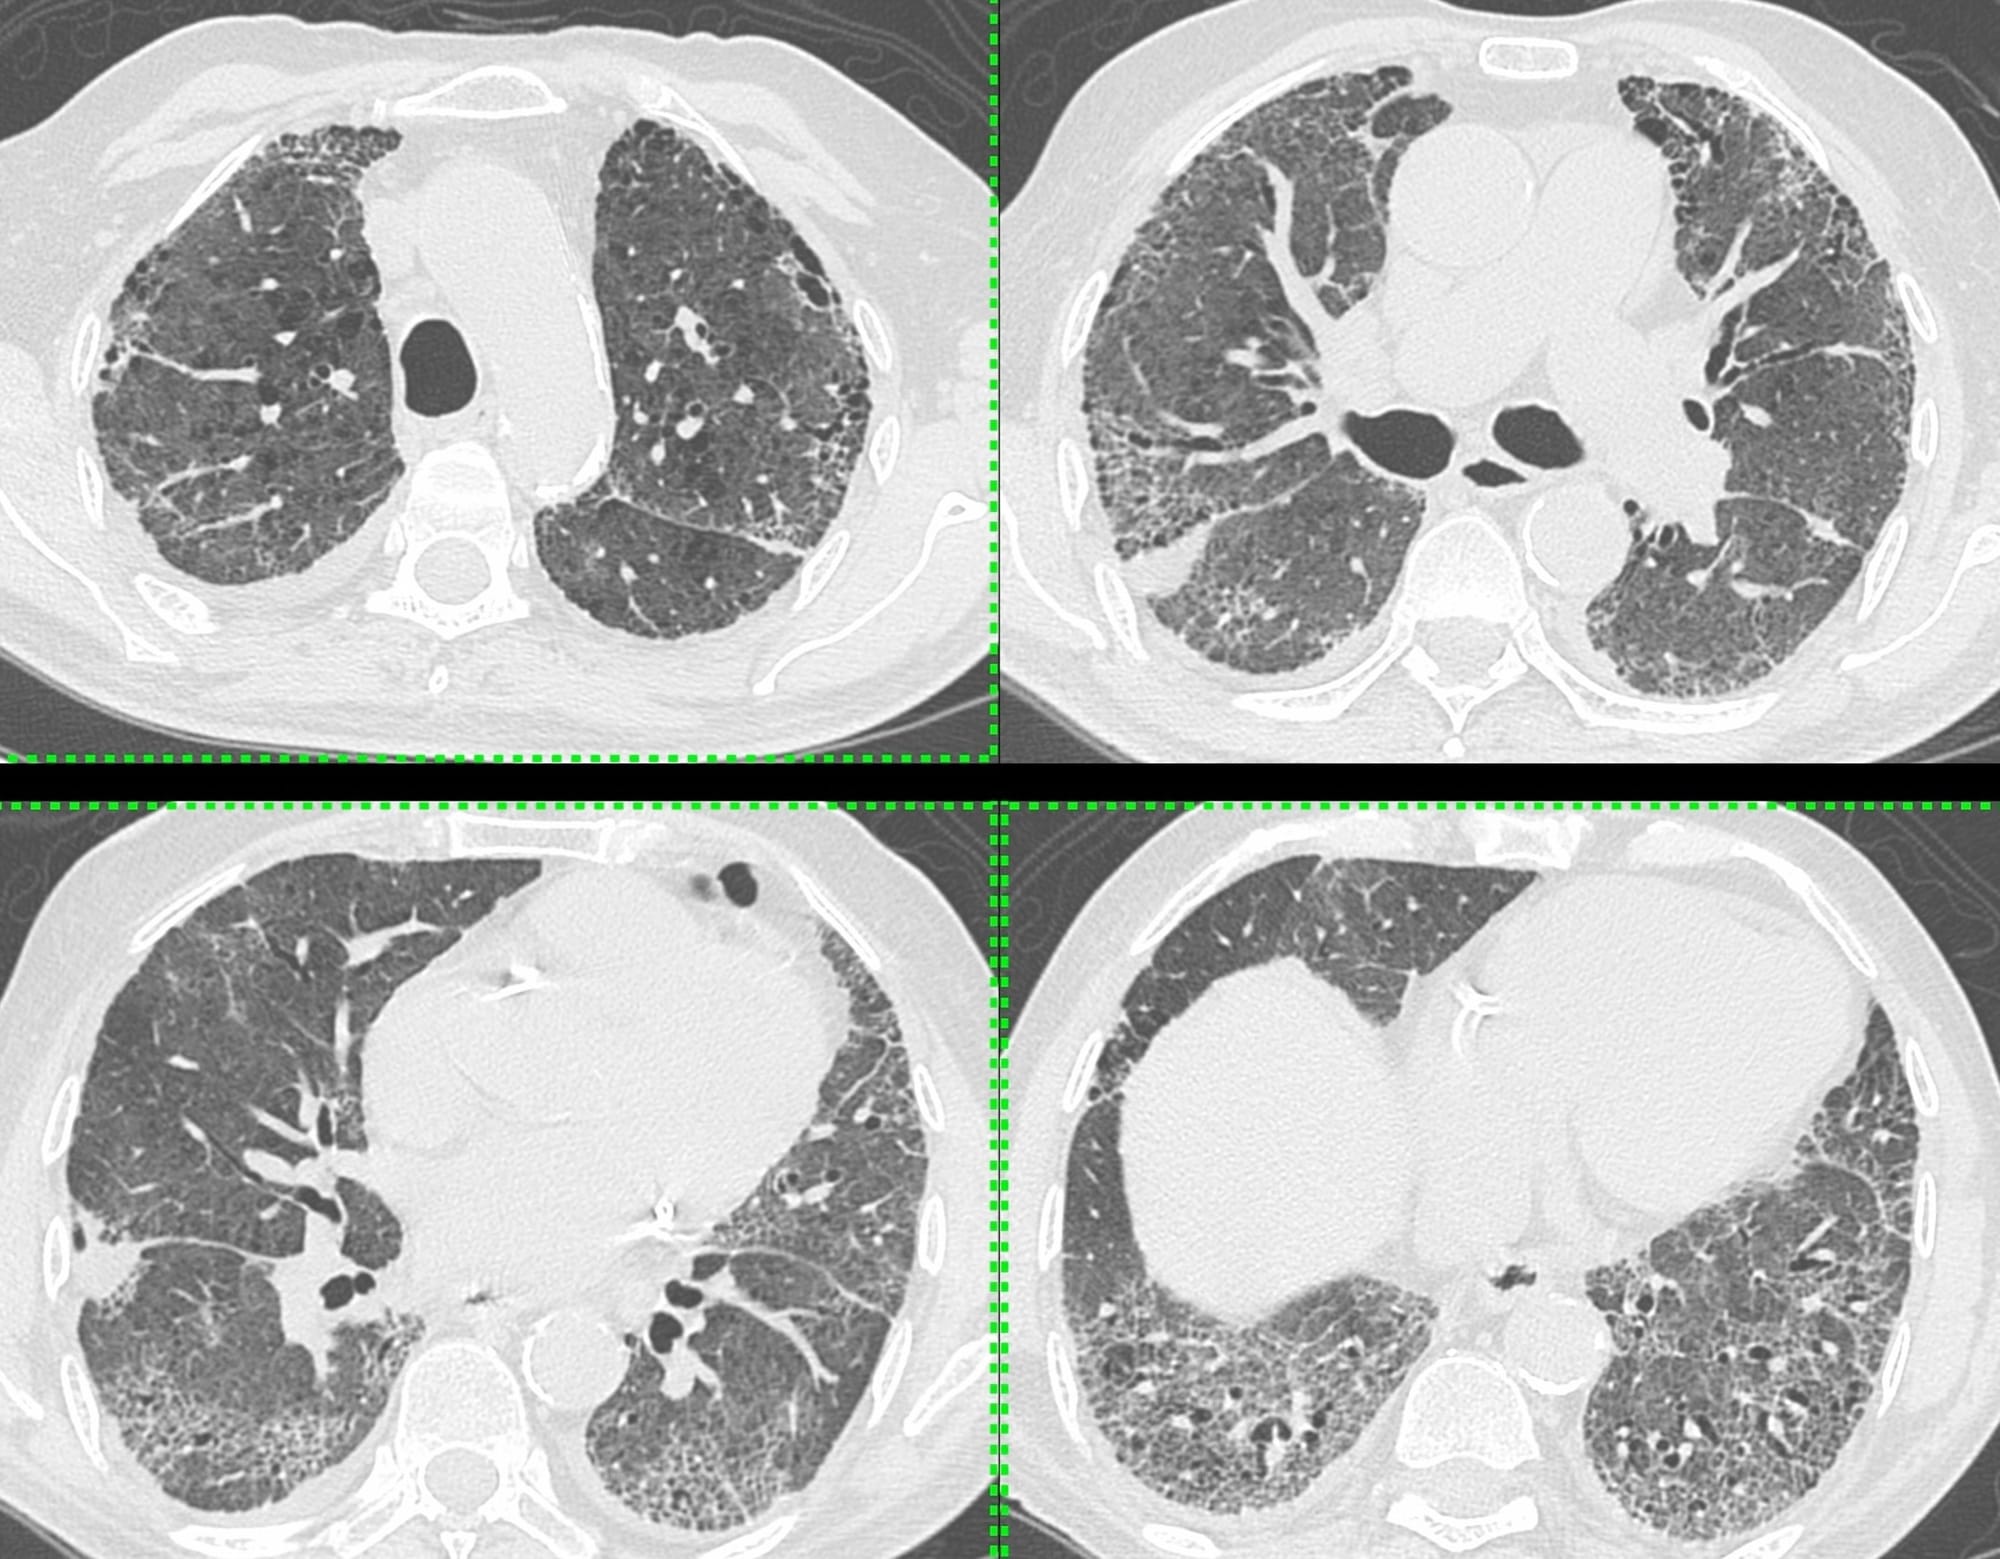

A 69-years old ex-smoker presented with breathlessness in 2020.

He had UIP/IPF.

One day in 2024, he presented with acute increased dyspnea.

- Acute exacerbation

- Acute infection

- Pulmonary edema/cardiac failure?